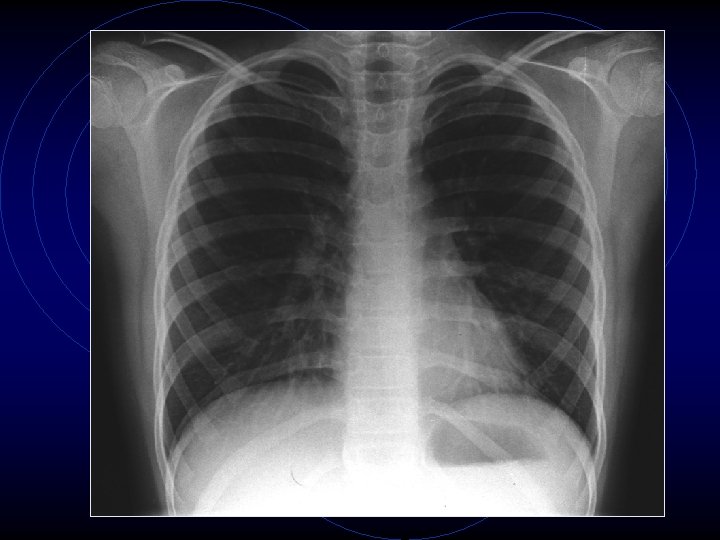

• Le indagini ematochimiche evidenziavano una modesta leucocitosi neutrofila (GB: 13340, N: 89, 3%) con PCR nei limiti della norma (< 0, 46 mg/dl) così come transaminasi, ionogramma, glicemia, azotemia, creatininemia, elettroforesi delle proteine • Veniva quindi eseguita radiografia del torace che dimostrava una modesta iperespansione dei campi polmonari bilateralmente con accentuazione del disegno polmonare